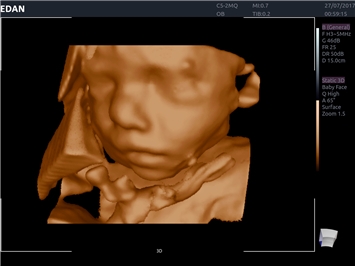

EDAN Acclarix LX4

Расширьте свои представления. Использование усовершенствованной платформой Acclarix система LX4 обеспечивает непревзойденную четкость изображений и интеллектуальный рабочий процесс для всех пользователей, являясь при этом наиболее экономичным решением.

EDAN Acclarix LX4 представляет собой инновационную ультразвуковую систему, построенную на усовершенствованной платформе Acclarix. Сочетание высокого качества визуализации с интеллектуальным рабочим процессом делает эту систему оптимальным выбором для клиник, ценящих эффективность и экономичность.

• 3D/4D-визуализация с автоматическим редактированием объема (eFace)